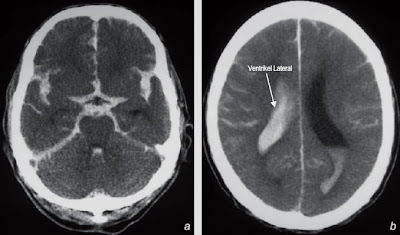

Cedera intrkarnial yang lain kadang juga dapat terjadi.(6) Perdarahan subarachnoid, dapat diidentifikasi pada CT-scan sebagai jaringan dengan densitas tinggi (40 – 90 Hu). Menggantikan cairan serebrospinal di interhemisfer atau fissura silvii, sulcus cerebral atau sisterna basalis. Jika pendarahan subarachnoid luas maka bentuk arah infundibulum atau cabang arteri karotis pada sisterna nampak sebagai filing deffect pada darah intrasisternal yang hiperdens. Meskipun pemeriksaan CT-scan sangat akurat untuk mendeteksi pendarahan subarachnoid yang baru untuk mengetahui adanya darah disubarachnoid di interhemisferik falxcerebri yang relatif memiliki densitas dan sulit dideteksi. Blog ini bukanlah kumpulan wahyu Ilahiah ataupun kebenaran ilmiah yang tak dapat terbantahkan. Di beberapa postingan bisa saja terselip racun atau sampah yang dapat merusak hidup Anda.